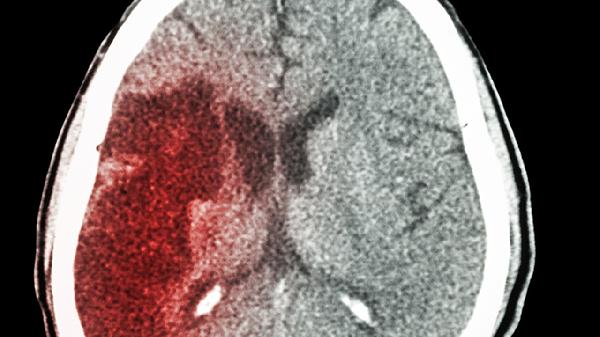

脑血管畸形导致脑出血如何治疗

脑血管畸形导致脑出血的治疗方式主要有手术切除、血管内介入治疗、立体定向放射治疗、药物治疗和康复治疗。脑血管畸形可能与先天性血管发育异常、高血压等因素有关,通常表现为突发头痛、呕吐、意识障碍等症状。建议及时就医,根据病情选择个体化治疗方案。